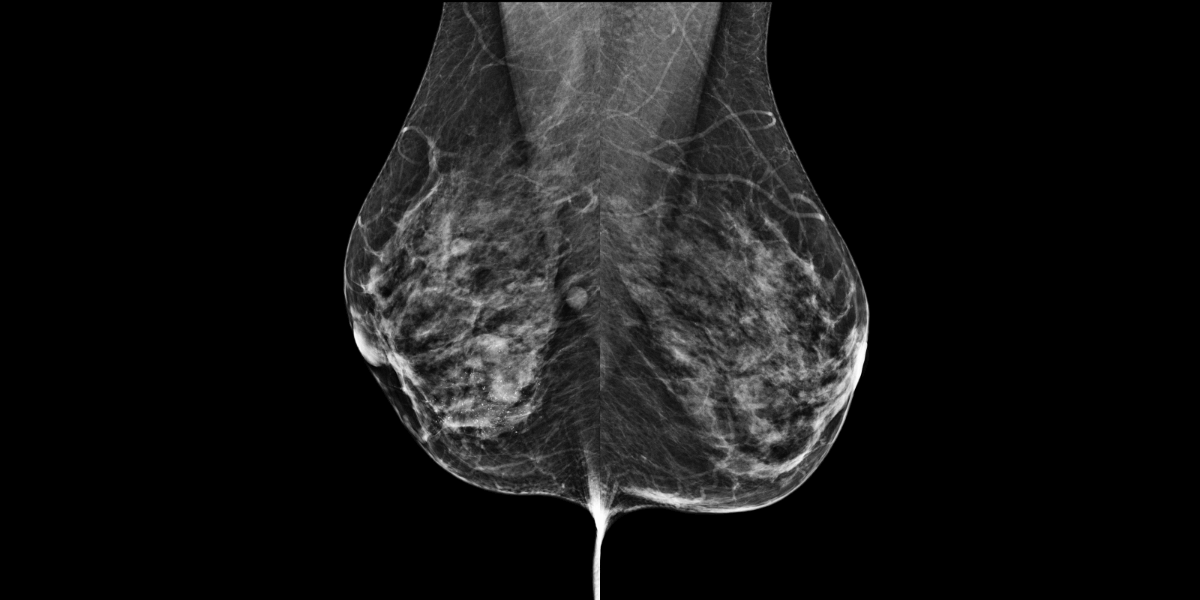

Femme de 46 ans vient pour une masse du quadrant infero interne du sein droit.

MammoScreen™ pointe des surcroit de densité du sein droit.

Mais MammoScreen™ pointe aussi un foyer de microcalcification supéro externe du sein controlatéral.

Les microcalcifications sont poussiéreuses, macrobiopsie en attente.